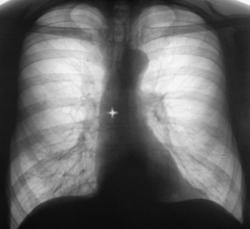

Иллюстрации 4, 5. На обзорной рентгенограмме органов грудной полости, произведенной в прямой проекции, в дополнении к скиалогической картине, полученной при цифровой флюорограмме добавлено — некоторое смещение верхнего средостения вправо с учетом смещения «просвета трахеи». При детальном исследовании области правого корня дополнительной информации не выявлено.